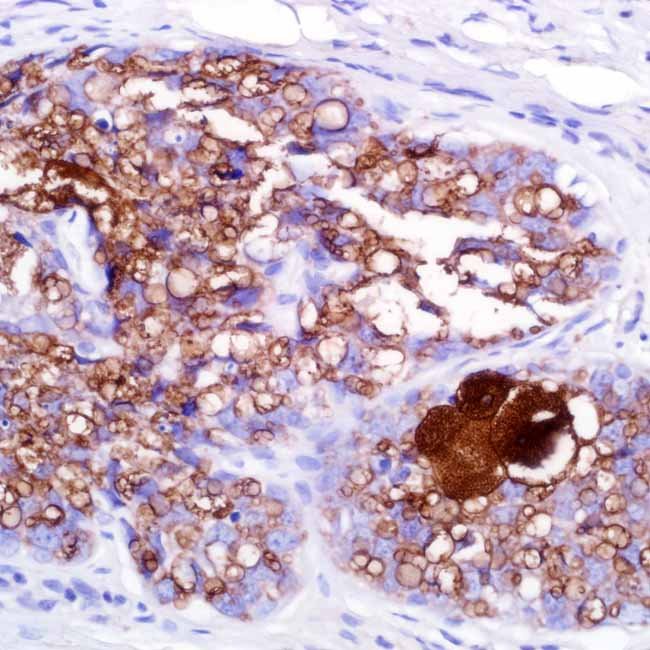

Adipophilin (Polyclonal)

Anti-adipophilin targets the PLIN2 (perilipin 2) protein,which is a member of the perilipin family and is linked tointracellular lipid storage droplets and lipid globule surfacemembranes in a variety of normal cells. When identifyingintracytoplasmic lipids, which are present in sebaceouslesions, it is useful. Because it can be used to designatesebocytes, anti-adipophilin is useful for identifyingsebaceous cancer.

ControlSebaceous neoplasms